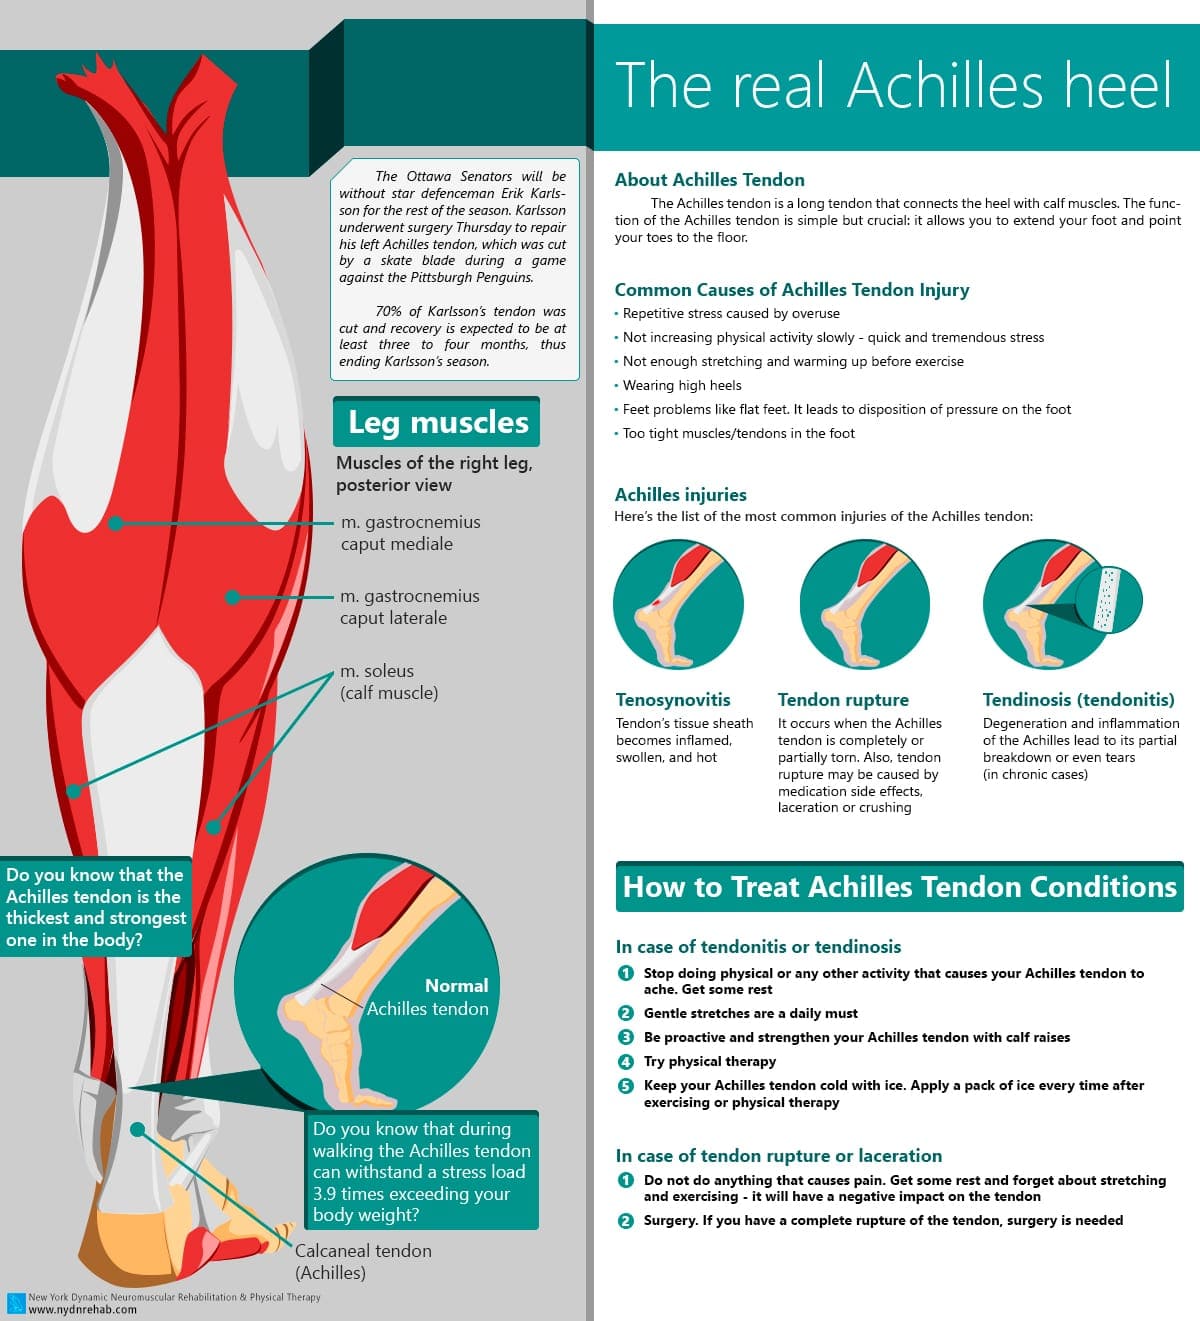

pictures of achilles tendon

Achilles Tendon – Squat University

Feel Better Now Series – How To Treat Achilles Tendinitis – Best home …

Treatment options for chronic Achilles tendon disorders

Achilles Tendon Rupture Information and Help SportNova UK – DaftSex HD

Achilles Tendonitis Treatment Bondi Junction, Barangaroo (Sydney CBD …

Achilles Tendon Tears | Jacksonville Orthopaedic Institute

ACHILLES TENDINOPATHY – Step Relief Podiatry

Achilles tendinitis – Mayo Clinic

Achilles Tendonitis Pain Management | Dr. Scholl’s

Achilles Heel, Achilles Tendon, Achilles Tendonitis Explained. Achilles …

💥𝐀𝐜𝐡𝐢𝐥𝐥𝐞𝐬 𝐓𝐞𝐧𝐝𝐢𝐧𝐨𝐩𝐚𝐭𝐡𝐲💥 ——— 👣Achilles tendinopathy describes a …

What is Achilles Tendinopathy? – Insoles and Orthotics – Healthy Step

Achilles Tendinopathy (Tendinitis and Tendinosis) – Complete Feet …

Achilles Tendinitis: Causes, Picture, Symptoms And Treatment

Achilles Tendonitis Causes, Symptoms & Treatment

Common Injuries of the Achilles Tendon – Osteopathy Singapore

Achilles Tendinitis – OrthoInfo – AAOS

Achilles Tendonitis / Tendonosis